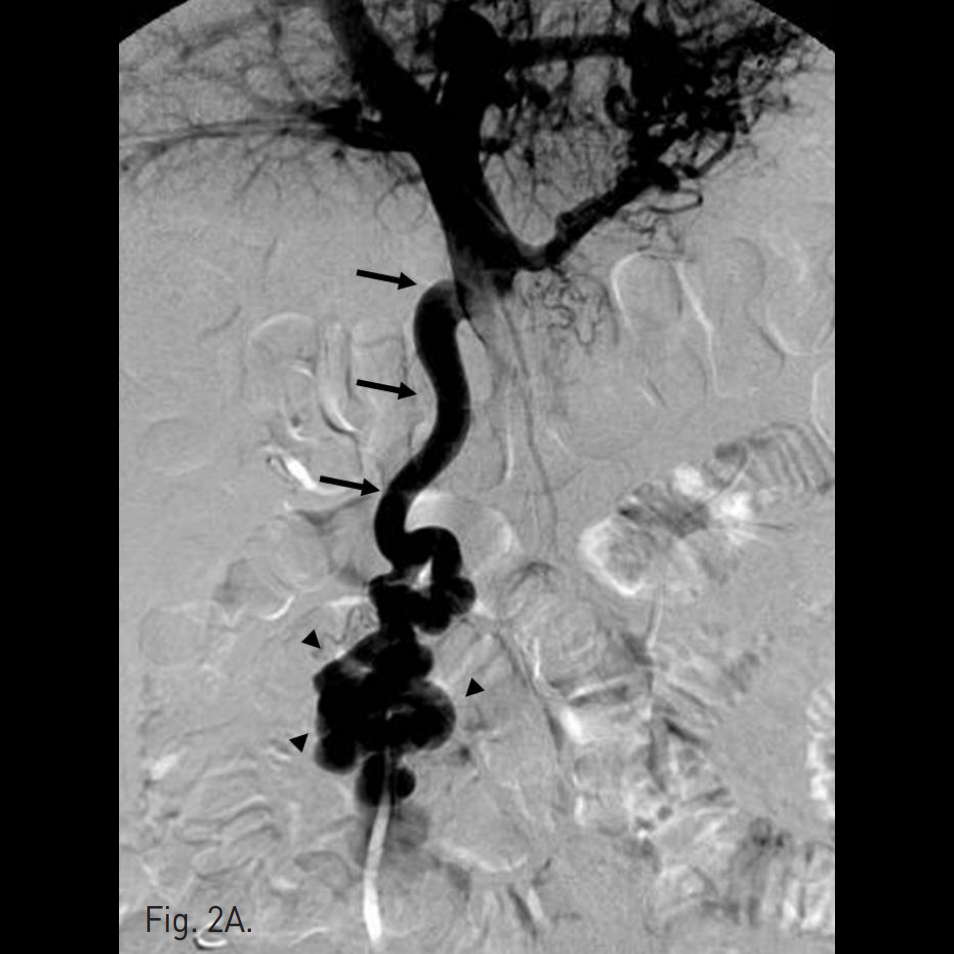

우후간문맥(right posterior portal vein)을 경피적으로 천자하여 6F sheath를 삽입하고 5F curved diagnostic cahteter를 상장간막정맥(superior mesenteric vein, SMV)에 위치시킨 뒤 시행한 direct portal venogram에서 주문맥(main portal vein)의 원위부에서 기시하는 비후된 혈관이 관찰되고 jejunal varix와 연결되어 있으며, 주문맥으로부터 다량의 혈류가 이 혈관으로 역류하고 있음(Fig. 2A). Varix의 nidus로부터 기시하는 drainage veins가 다수 관찰되고, 그 중 varix의 기시부에서 하대정맥으로 직접 유출되는 다량의 혈류가 있음(Fig. 2B).

Fig. 2

A. Direct portal venogram shows large amount of portal flow refluxed into hypertrophied vein (arrows) originated from distal portion of main portal vein, which supplies huge jejunal varix (arrowhead) without definitive con trast extravasation.

B. Multiple draining veins (arrows) from nidus of varix are found and one of them is hypertrophied and drained directly into IVC.